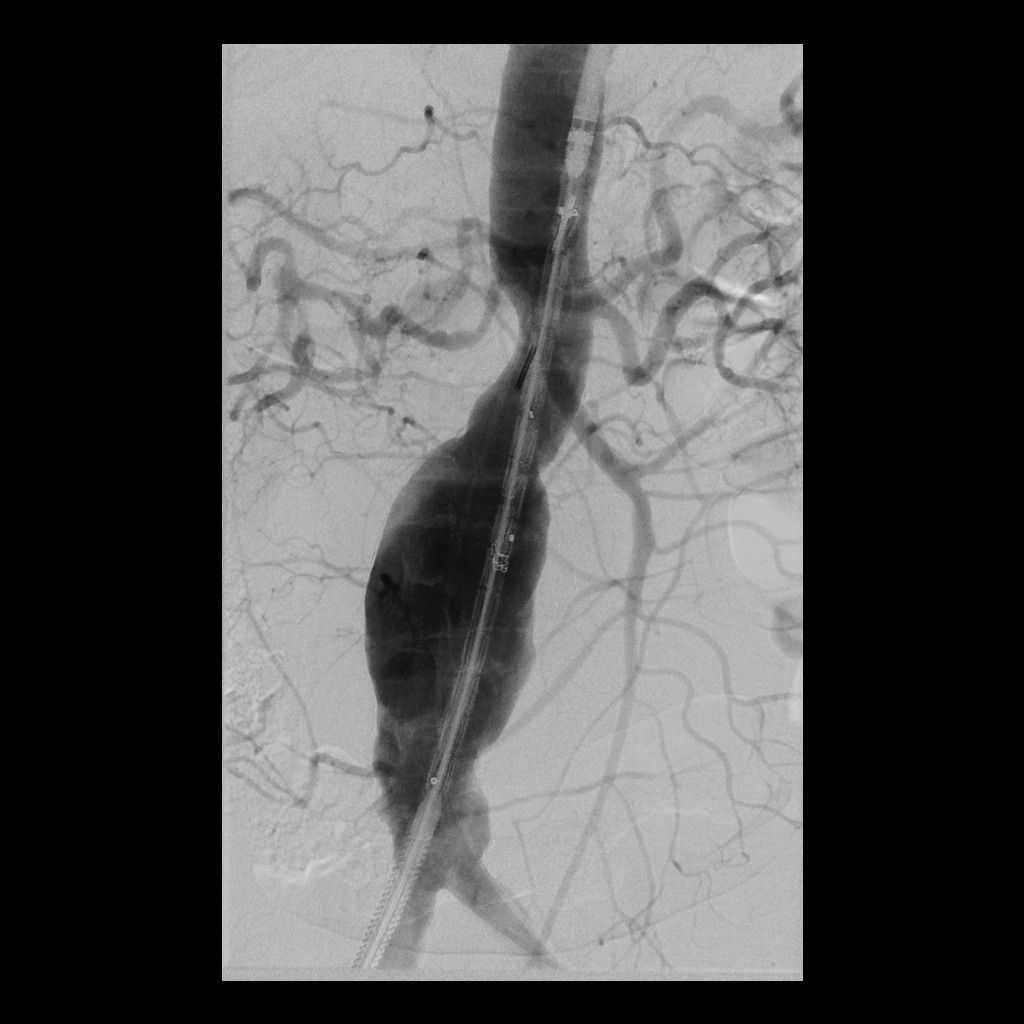

Bauchschlagadererweiterung (Aortenaneurysma)

Eine Erweiterung der Bauchschlagader kann das Risiko eines Gefäßeinrisses stark erhöhen (Aneurysma). Die Radiologie bietet hier zusammen mit den Kollegen der Gefäßchirurgie ein minimal-invasives Verfahren zur Ausschaltung des Aneurysmas an. Dies geschieht mittels Stent-Prothese (endovascular aortic repair; EVAR).